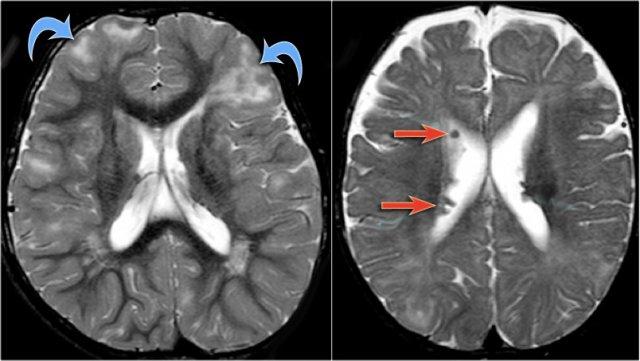

Hình ảnh T2W và FLAIR mặt phẳng coronal cho thấy xơ cứng thùy thái dương trong bên phải.

Lưu ý tình trạng mất thể tích, biểu hiện của teo não, gây giãn thứ phát sừng thái dương của não thất bên.

Tín hiệu cao trong hải mã phản ánh tình trạng gliosis.

Hình ảnh cho thấy xơ cứng thùy thái dương trong với hải mã tăng tín hiệu và teo nhỏ (mũi tên đỏ), kèm theo giãn thứ phát sừng thái dương trái của não thất bên trái.

Cũng cần lưu ý tình trạng tăng tín hiệu dưới vỏ não kết hợp ở thùy thái dương trái, gợi ý loạn sản vỏ não khu trú.